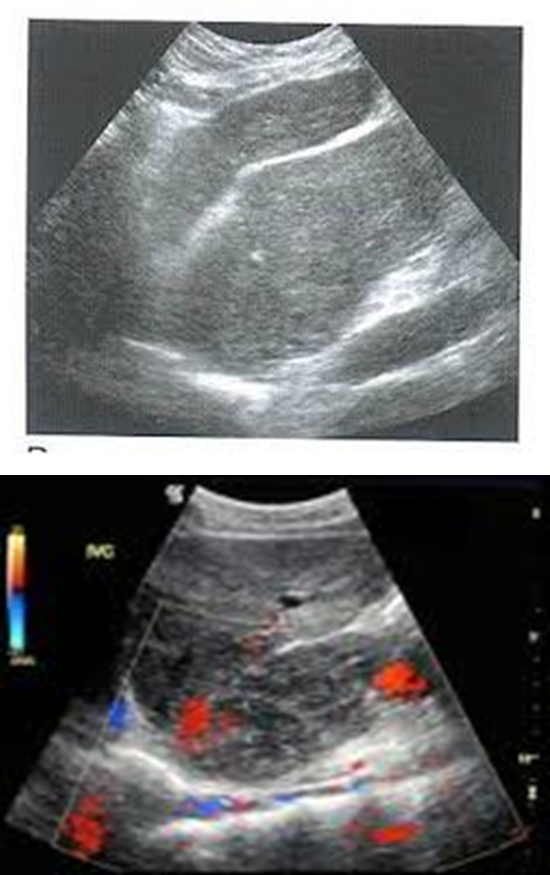

acute hepatitis sonographic appearance

hypoechoic

periportal cuffing (starry sky)

starry sky occurs due to

acute hepatitis

starry sky

likely due to acute hepatitis

acute hepatitis with starry sky

starry sky aka

periportal cuffing